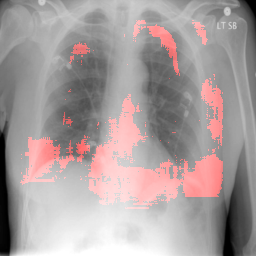

In order to test the effectiveness of the localization procedure in areas other than the heart region, we chose pulmonary edema which occurs in the lung region. Also, pulmonary edema is detected by the net like white structure in the lung area. No anatomical shape change is associated with the abnormality. We have found that the localization is obtained best when the ROIs of lungs are taken to compute the map. Following the scheme in section 3.4, localization experiment on pulmonary edema is performed as shown in Fig. 8. It has been observed that the classifier is not sensitive to the fine features like septal or Kerley B lines. The localization is mainly obtained in the lung region where excess fluid is observed. Some localization regions are outside the lung region which occurs primarily for the fact that, even though the occlusion center is outside the lung, it occludes lung region and thus the probability drop occurs.

In this section we show more examples of localization. Few localization samples are shown in Fig. 11. It can be observed that, in the CXRs with Cardiomegaly (Fig. 11(a) and (b)) a fine localization around the heart is observed. In the normal CXRs (Fig. 11(c) and (d)) such localization is not observed. Rather the lowest probabilities are spread out in the CXR image. It is interesting to note that, the localization algorithm gets low probability where the heart is enlarged during cardiomegaly, but the proportion is small compared to the localization in other areas of normal CXRs. In order to observe the performance of the heat map we computed histograms of heat maps of each of the 100 CXRs in the test set for Cardiomegaly detection and average histograms are shown in Fig. 11(e) and (f) for CXRs with Cardiomegaly and normal CXRs, respectively. It is to be noted that, the histograms include both success and failure cases. It can be observed that, for CXRs with Cardiomegaly the classifier is highly sensitive toward Cardiomegaly detection even under occlusion. This indicates that, the classifier primarily looks for local features in a CXR instead of some feature that is spread out in the entire CXR. However, the classifier is not sensitive toward normal CXRs under occlusion. Rather, the probabilities are spread out in the probability spectrum. After that, we analyzed the failure cases where the classifier is unable to classify the image correctly. Two such examples of failure cases are shown in Fig. 12. The localized CXR shown in Fig. 12(a) contains Cardiomegaly whereas the classifier detects it as normal. However, the localization shows that it localizes around heart quite well despite the in accurate classification. On the other hand, Fig. 12(b) shows an example of normal image which has been classified as Cardiomegaly by the classifier. There is stronger localization around the hear that that is observed for normal images as in Fig. 11(c) and (d), however, like those images the localization is spread out.

In a similar fashion, additional localization results for Pulmonary Edema is shown in Fig. 13. In Fig. 13(a) and (b) localization of two examples of CXRs with Pulmonary Edema is shown. As stated earlier the classifier localizes in the lung region. This is not the case when normal images are used to localize Pulmonary Edema as seen in Fig. 13(c) and (d). The localizations are obtained in random dense locations such as the sternum or heart. Like the cardiomegaly case, the histogram averages for CXRs with pulmonary Edema (Fig. 13(e)) shows a sensitivity toward pulmonary edema detection while the normal CXRs shows a spread out detection. It is interesting to note that, in the histogram of normal images high probability (¿0.85) is non-existent, thus ensuring low false positive rate. In the test set none of the normal images have been diagnosed as Pulmonary Edema. The failure cases are shown in Fig. 12. These CXRs are with Pulmonary Edema. However, the localization algorithm shows that one of them localizes in lungs whereas the other one shows a localization pattern similar to that obtained in normal CXRs.